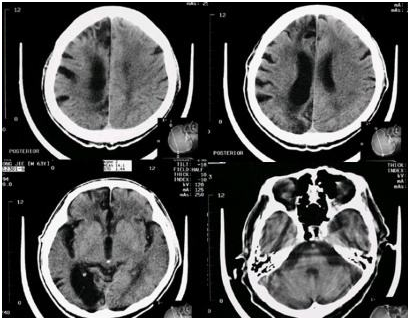

当时在医院所拍的片子